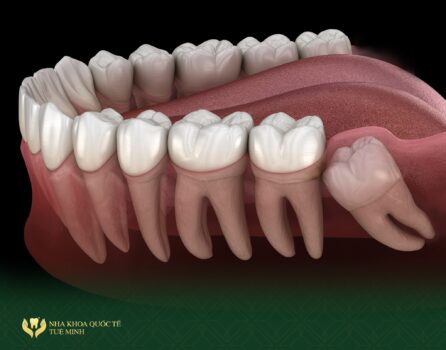

- Nhổ Răng Khôn

- Răng khôn, còn gọi là răng số 8, thường mọc muộn và có thể gây đau đớn hoặc cản trở chức năng nhai. Nếu răng khôn mọc ngầm hoặc lệch, việc nhổ răng khôn là cần thiết để tránh các vấn đề như viêm nhiễm hoặc ảnh hưởng đến các răng khác.